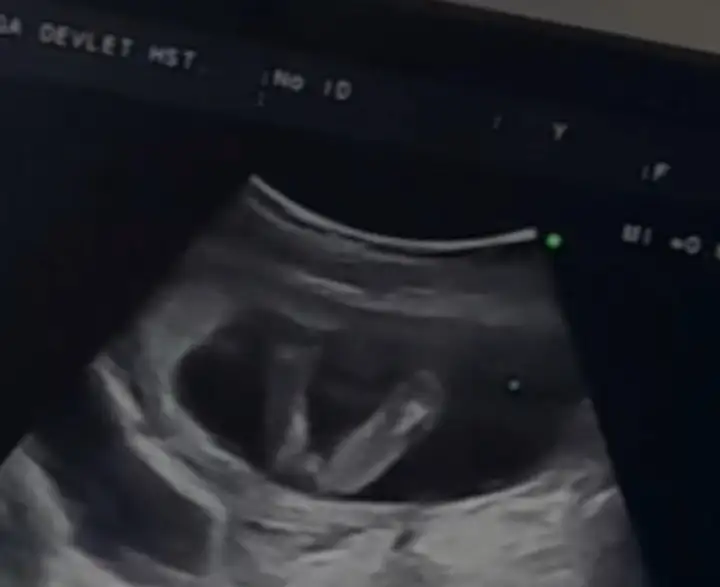

Kuş gibi duruyor sanki. Nub yukarı doğru kalkık oluyor erkeklerde kızlarda yatay şekilde paralel oluyor. Ayyyy neyse ne boşverin sağlıkla gelsin de ama yinede inşallah kalbinizden geçen olur. Kaçıncı hamileliğiniz?10 haftalıksınız öğrendim. Şu resim var elimde nub belli mi anlamadım ama 11 haftalık. Bir ay daha beklemek ne yorucu

İlk hamilelik.Kuş gibi duruyor sanki. Nub yukarı doğru kalkık oluyor erkeklerde kızlarda yatay şekilde paralel oluyor. Ayyyy neyse ne boşverin sağlıkla gelsin de ama yinede inşallah kalbinizden geçen olur. Kaçıncı hamileliğiniz?